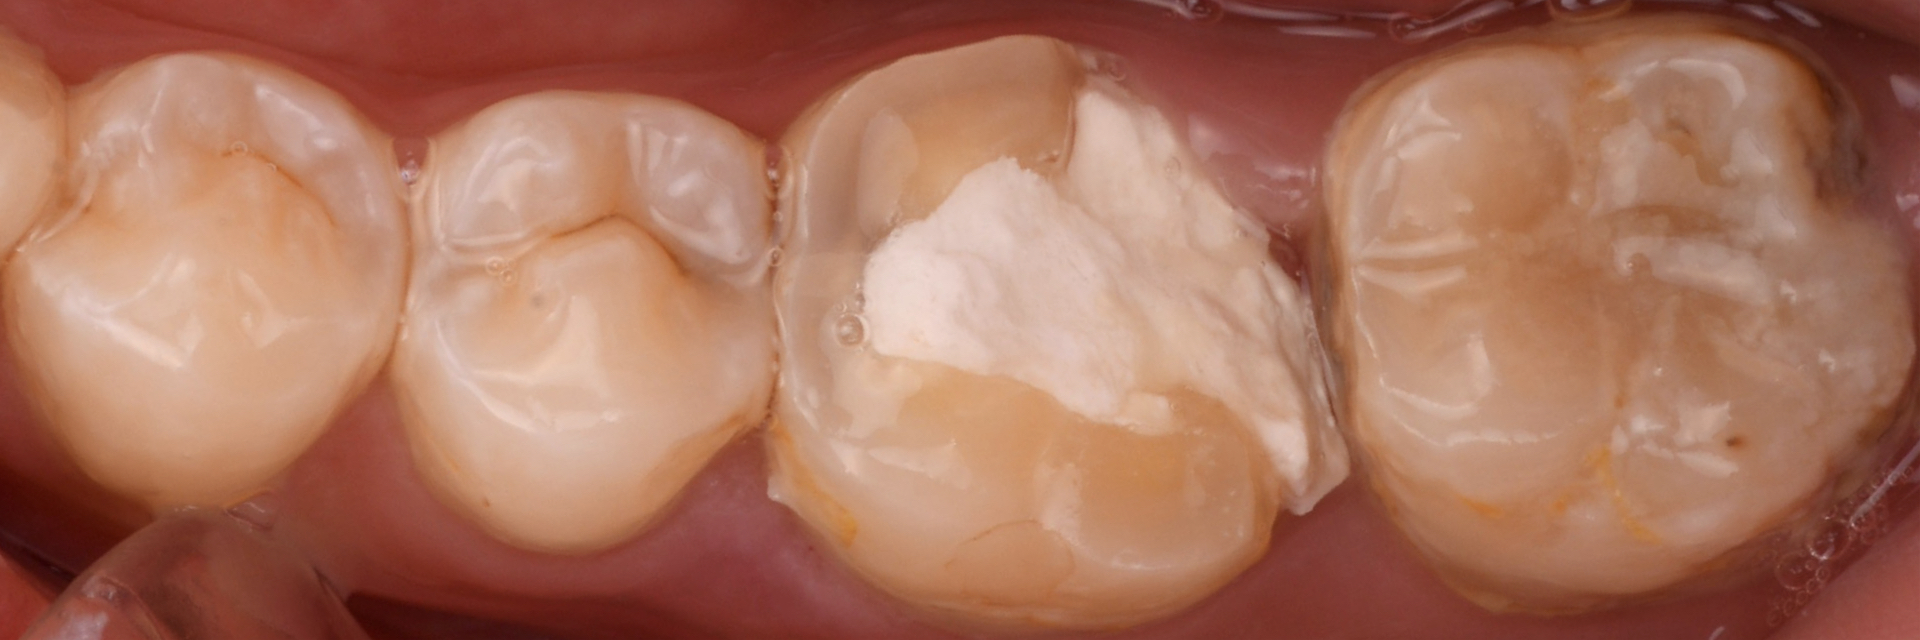

治療前